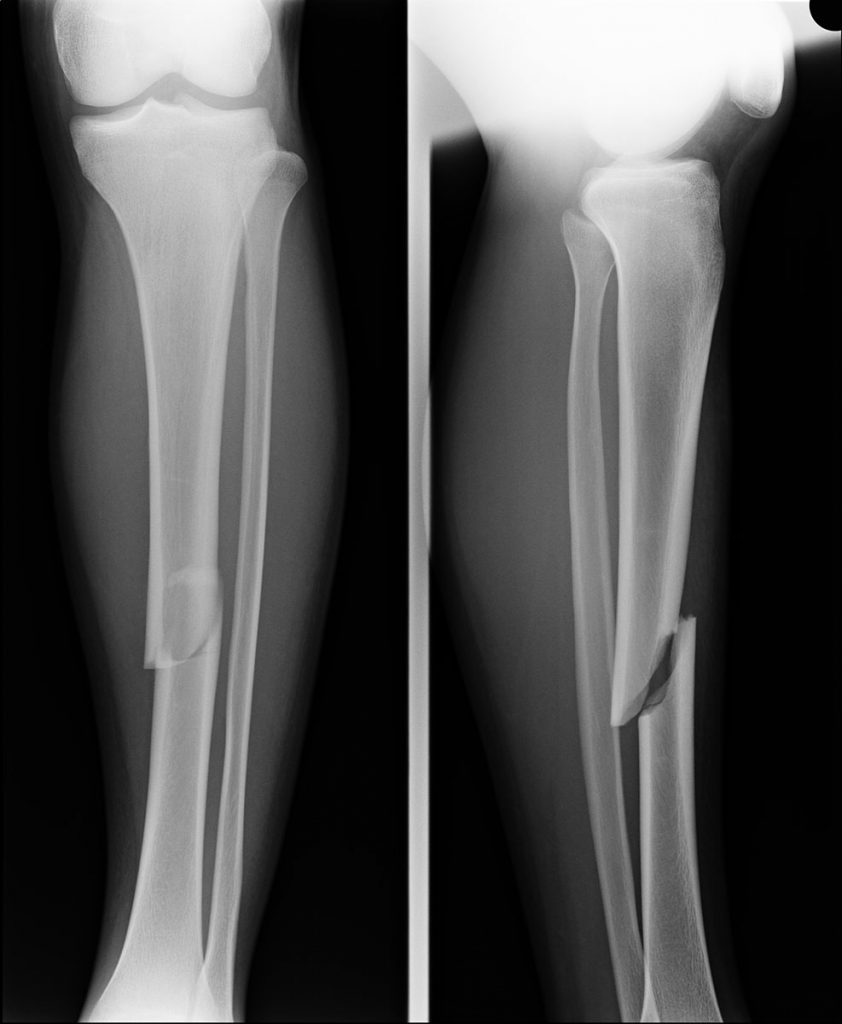

Tibial Stress Fractures The Bone School

Learning Radiology Stress Fracture, Tibia How Long For Stress Fracture In Tibia To Heal A tibial shaft stress fracture is an overuse injury where normal or abnormal bone is subjected to repetitive stress, resulting in microfractures. It can be difficult to distinguish a tibial stress fracture from a case of shin splints. Stress fractures of the tibia are typically caused by too much stress placed on. doctors can sometimes diagnose a stress fracture. How Long For Stress Fracture In Tibia To Heal.